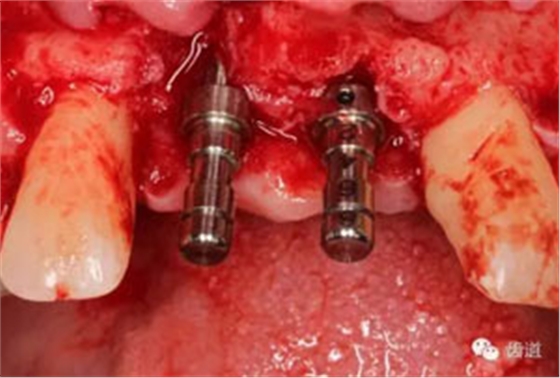

患者對(duì)美觀要求較高,與患者溝通后,擬定采用骨環(huán)技術(shù),同期種植并增加骨寬度和高度。

患者不愿才用自體骨移植,遂建議采用同種異體骨骨塊(皮質(zhì)骨)進(jìn)行骨環(huán)手術(shù)。 種植手術(shù):

骨環(huán)技術(shù)可以解決水平和垂直向的骨不足,但一般采用自體骨。自體骨雖然是骨移植的金標(biāo)準(zhǔn),但是需要在第二術(shù)區(qū)取骨,患者疼苦較大。同種異體骨塊來(lái)自于人類,和自體骨的結(jié)構(gòu)非常類似,成骨性能良好。故筆者選用同種異體骨塊進(jìn)行骨環(huán)手術(shù),在國(guó)內(nèi)外都是首次。該病例筆者隨訪觀察了一年,目前骨環(huán)比較穩(wěn)定。 白石 男 重慶醫(yī)科大學(xué)附屬口腔醫(yī)院種植科主治醫(yī)師,講師,碩士; 國(guó)際種植協(xié)會(huì)高級(jí)??漆t(yī)師,華西口腔醫(yī)學(xué)院碩士畢業(yè)生; 從事種植外科和種植修復(fù)臨床工作10年; 曾接受系統(tǒng)化種植培訓(xùn),有豐富口腔種植治療經(jīng)驗(yàn),擅長(zhǎng)復(fù)雜種植的設(shè)計(jì)與修復(fù),對(duì)全口種植義齒、種植美學(xué)修復(fù)技術(shù)和常規(guī)精密義齒修復(fù)有較深研究。 參加國(guó)內(nèi)外多次會(huì)議,并屢次獲得病例比賽獎(jiǎng)勵(lì)。